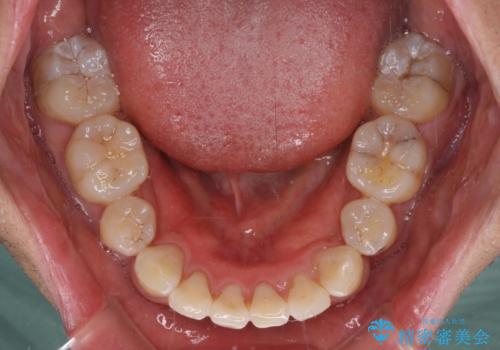

奥歯の咬み合わせを改善したいため、治療期間が長くなりましたが、患者様には辛抱強くお付き合いいただきました。

上下の正中を合わせることもでき、患者様には大変満足していただきました。